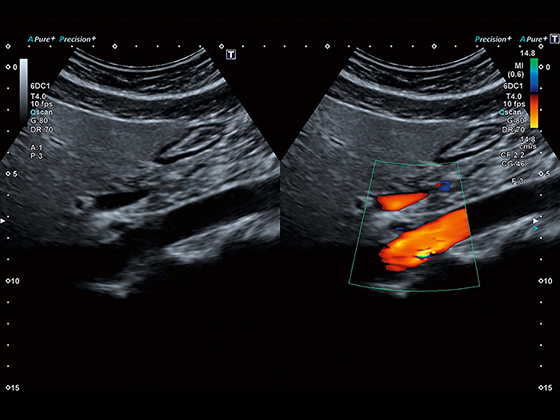

Кольорове допплерівське картування

Енергетичний допплерівський режим